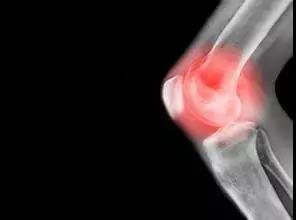

什么样的骨刺才需要治疗?

- 凡事都两面性,骨刺也一样。当关节软骨遭受破坏,机体修复性地长出了“骨刺”后,其实是为了提升整体的稳定性,避免继续遭到损伤。大部分情况下,人体并不会对细小的骨刺感到有什么不适感,只有当进行影像学检查后才发现存在骨刺。

- 发生骨质增生后,随着关节用的次数继续增加,导致构成关节的各种组织如软骨等就会很大概率出现老化、发炎等反应,这些变化导致关节周围的组织受刺激或者受压迫,从而引起肿胀疼痛等一系列症状,如颈痛、腰痛、肢体疼痛或神经疼痛、关节疼痛等,这个时候骨刺就需要治疗了。